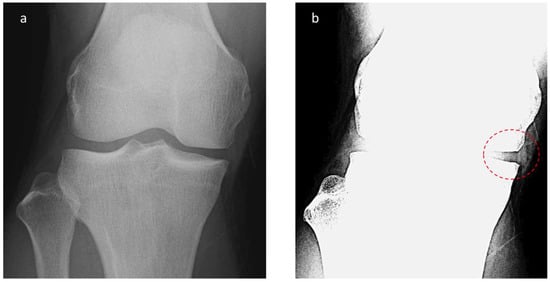

The MME length on radiographic images was investigated as follows. First, radiographs scanned in the knee anterior–posterior direction without weight bearing were subjected to appropriate window processing (specifically, narrowing the window width) to enable the medial meniscus to be more easily visualized (Figure 2). Next, the amount of MME (X-MME) from the medial margin of the tibia, excluding osteophytes (extrusion length) was measured (Figure 3), as was the height of the meniscus at the medial margin of the tibia, excluding osteophytes on X-ray (X-HMM) (Figure 4). Finally, the meniscal extrusion ratio was calculated by dividing the meniscal extrusion length by the meniscal height (X-MER) (Figure 5). Prior to these measurements, a small workshop to ascertain the appropriate gradation processing of radiographic images for use in meniscal measurements was conducted, using a radiology workstation (Synapse® Cardiovascular Picture Archiving and Communication System (PACS) (Fujifilm, Tokyo, Japan)). After the appropriate gradation processing method for measurements of MME length and meniscal height had been confirmed, two orthopedic surgeons specializing in the knee each made two sets of measurements, and intra-investigator reliability and inter-investigator reliability were calculated.

Figure 2. Radiographic appearance of meniscal extrusion. (a) Anteroposterior (AP) view knee radiograph with standard window settings. (b) AP knee radiograph with narrow window settings demonstrates visualized meniscal tissue.